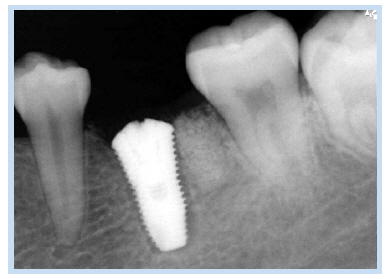

37세 여성이 오래 전에 발거한 하악 우측 제1대구치 위치의 무치악 부위 임플란트 식립 및 수복을 위하여 내원하였다. 파노라마 방사선 사진에서 하악 우측 제1대구치를 발치한 무치악 부위에 방사선 불투과상을 보이는 잔존 치근으로 추정되는 것이 관찰되었다(Fig. 13). 잔존 치근은 그대로 남겨둔 채로 임플란트를 식립하기로 계획하였다. 국소마취하에 치조정 절개 및 골 점막 피판을 거상하여 직경 4.5 mm 높이 10 mm의 임플란트를 식립하였다. 치유 지대주를 연결한 후 fixture의 근심 면의 협측에 골열개가 존재하여 분말형 자가치아골이식재를 이식하였다. 피판을 재위치시키고 4-0 Vicryl로 봉합하였다. 1주 후 봉합사를 제거하였고 치근단 방사선 사진을 촬영하였다(Fig. 14). 임플란트 식립 3개월 후에 최종 보철물을 장착하였고, 임플란트 식립 5개월 후 근심 측 식편압입을 호소하여 보철물을 다시 제작하여 장착하였다. 임플란트 식립 47개월 후에 촬영한 치근단 방사선 사진을 통해 안정적으로 임플란트가 유지되고 있음을 관찰할 수 있었다(Fig. 15, 16).

Fig. 14. Periapical radiograph 1 week after implant placement.